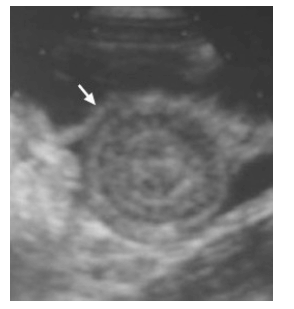

Uma criança de 9 meses de vida é levada ao pronto atendimento em razão de quadro de dor abdominal e fezes misturadas com sangue. Ao exame físico, nota-se massa abdominal palpável. É realizada ultrassonografia abdominal, representada na imagem. A criança apresenta FC= 110 bpm, FR = 25 irpm e saturação de oxigênio = 98% (ar ambiente).

Uma criança de 9 meses de vida é levada ao pronto atendimento em razão de quadro de dor abdominal e fezes misturadas com sangue. Ao exame físico, nota-se massa abdominal palpável. É realizada ultrassonografia abdominal, representada na imagem. A criança apresenta FC= 110 bpm, FR = 25 irpm e saturação de oxigênio = 98% (ar ambiente).

Uma criança de 9 meses de vida é levada ao pronto atendimento em razão de quadro de dor abdominal e fezes misturadas com sangue. Ao exame físico, nota-se massa abdominal palpável. É realizada ultrassonografia abdominal, representada na imagem. A criança apresenta FC= 110 bpm, FR = 25 irpm e saturação de oxigênio = 98% (ar ambiente).